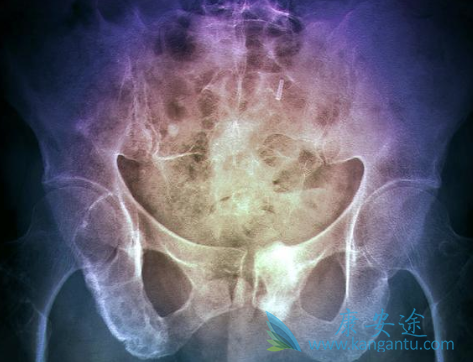

多发骨髓瘤